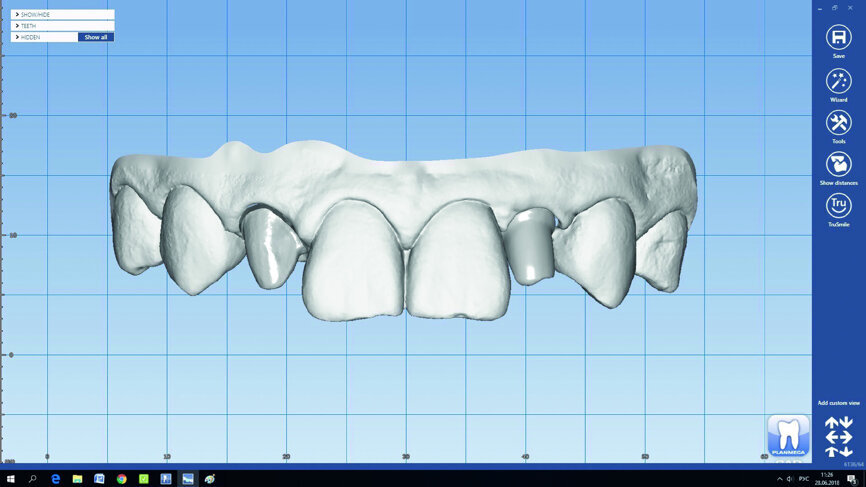

The clinical case illustrates the advantages of using Planmeca CAD/CAM solutions in the digital planning of an implant placement and surgical guide, as well as in the fabrication of a ceramic restoration. This article presents a clinical case in which the treatment was completed using the Planmeca Romexis 3D Implant Guide software, Planmeca PlanCAD Premium software and Planmeca PlanMill 40 milling unit.

Fig. 3: Digital implant and surgical guide planning in Planmeca Romexis software.

Fig. 4: Digital implant and surgical guide planning in Planmeca Romexis software.

In this particular case, we started with an aesthetic analysis of the patient’s CBCT data and concluded that a Straumann implant with a 2.9 mm diameter would fit in the area of tooth 22, if we used a surgical guide for maximum precision (Figs. 3–5). For tooth #12, we decided to fabricate a thin-walled IPS e.max ceramic restoration (Ivoclar Vivadent).